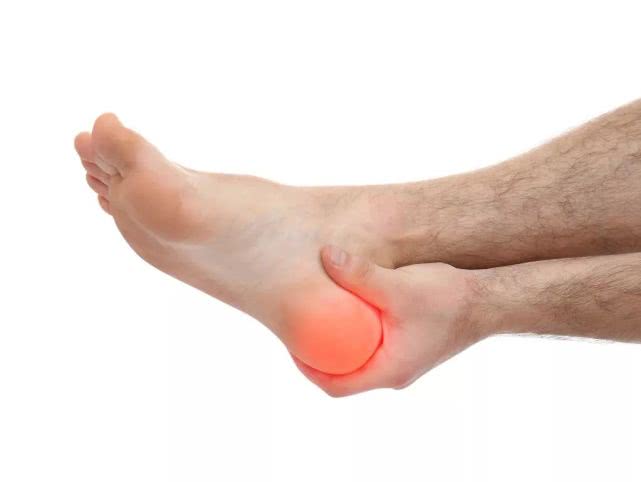

足跟痛(跟痛症)在中老年人群*特中**别常见,主要表现为足底刺痛感,负重行走加重,休息减轻,给患者生活和工作带来极大不便。本病的发生与劳损和退化等关系密切,多见于中老年,男多于女,单侧或双侧均可发病,也可发生于频繁体育运动的爱好者。足跟痛在临床上主要包括跟骨骨刺、跟部滑囊炎、跟腱炎、足底脂肪垫炎等。

图片来源于网络